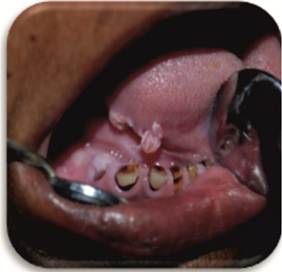

On examination an irregular whitish pink papillary proliferative growth, measuring approximately 1x0.5cm was noticed on the right lateral border of tongue and two lesions merging with each other (Figure 1). Lesion was sessile, non tender and fixed to right lateral border of the tongue. A clinical provisional diagnosis of papilloma of right lateral border of the tongue was considered.

Figure-1 showing whitish pink papillary proliferative growth on right lateral border of the tongue